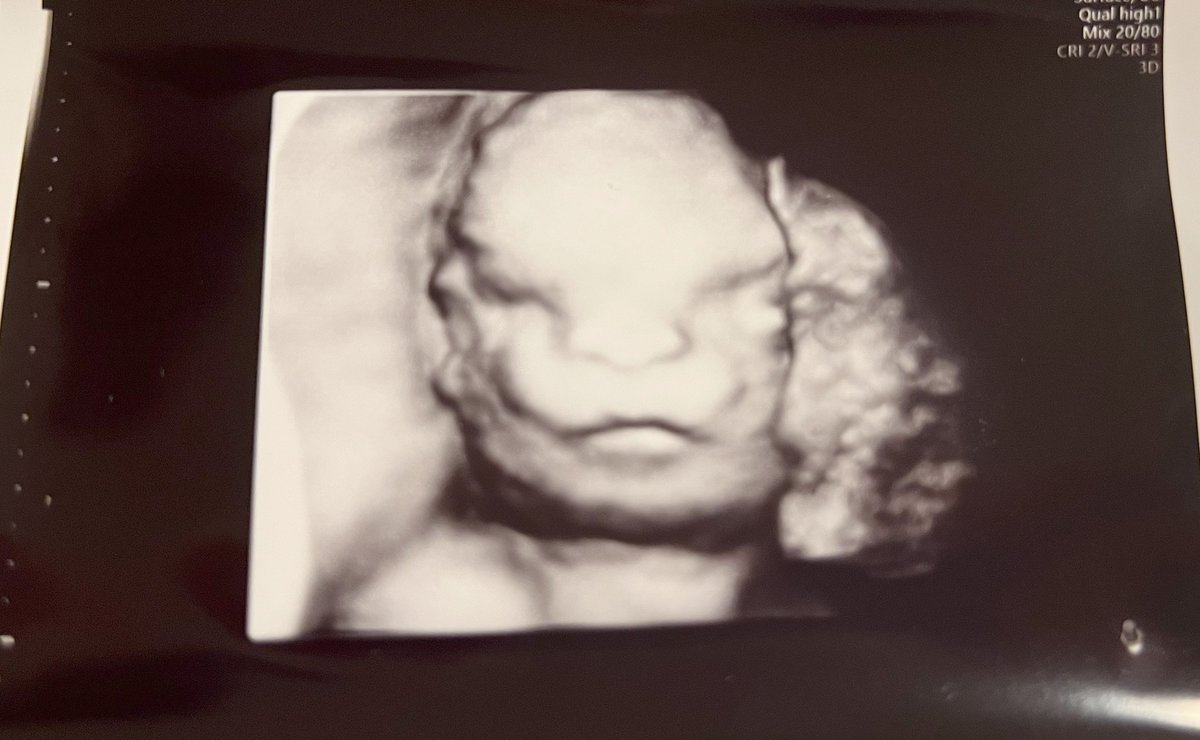

妊娠28週(妊娠8か月)のころのエコー画像

8/28